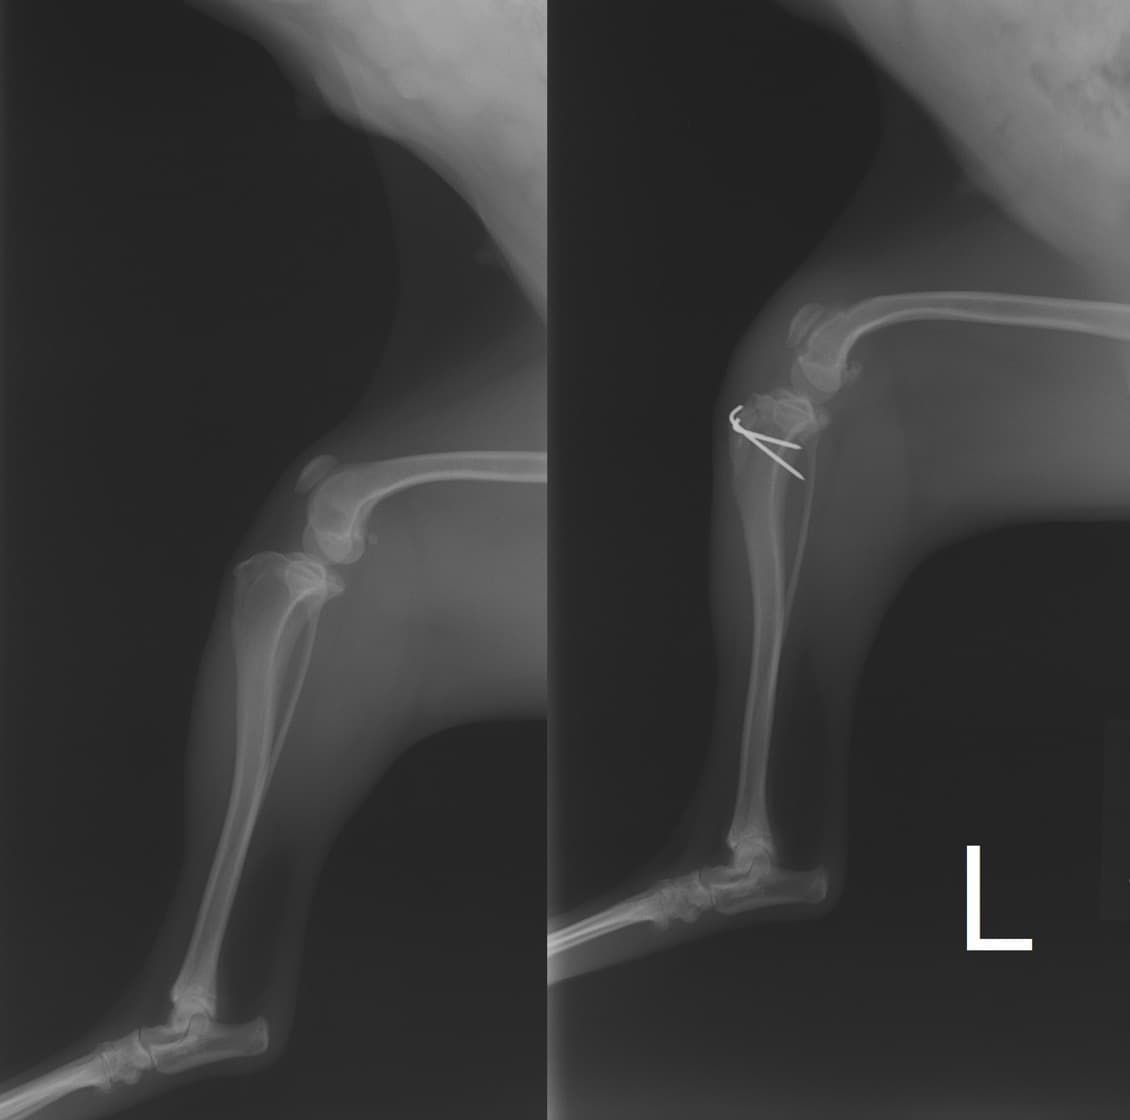

■ 症例22 ポメラニアン 1歳5か月 去勢雄

左後肢の挙上を主訴に来院した。整形学的検査、レントゲン検査より左右の膝蓋骨脱臼(左GradeⅡ〜Ⅲ、右Grade Ⅱ)を認めた。また、脛骨の前方引き出し試験の際に、引き出し兆候は認められないものの、疼痛が認められたため、前十字靭帯の損傷が疑われた。術中における、目視および関節内の操作によって、前十字靭帯の損傷や過伸展といった異常が認められなかったため、膝蓋骨脱臼の整復のみ実施した。手術手技は縫工筋及び内側広筋の解放、脛骨粗面の外側転位、滑車ブロック形造溝術、内外側関節包の縫縮を実施した。本症例は跛行もなく経過良好である。しかし、頸骨高平部の角度(TPA)が 右26.2°、左24.9°であり、解剖学的に前十字靭帯損傷のリスクが高いことから今後の経過に注意が必要である。